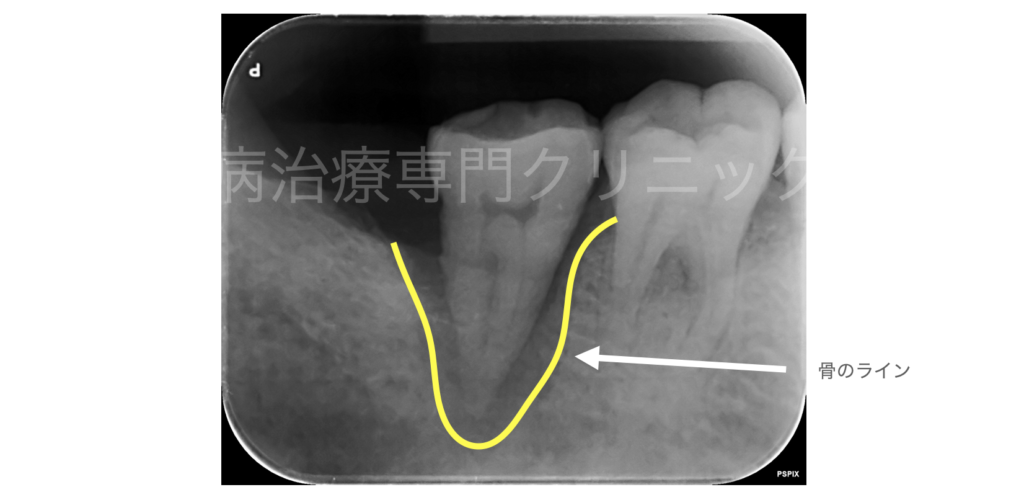

歯周組織再生療法は、すべての骨の吸収に対して行えるわけではなく、再生に適しているケースもあれば、そうでないケースもあります。

歯周組織再生治療を行うことで、このような骨欠損への回復が可能となります

歯周組織再生治療が可能な症例

歯周組織再生療法が難しい(再生が見込める可能性が低い)症例